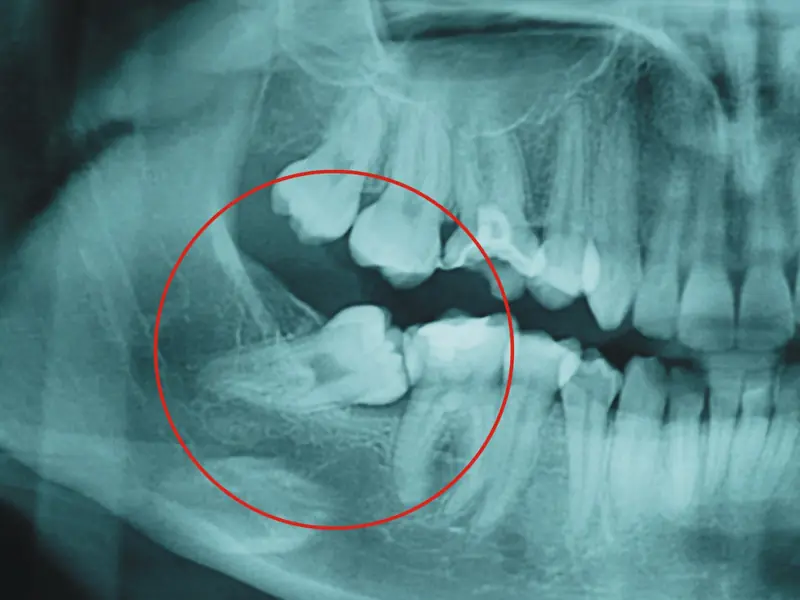

Esta semana hemos conocido una respuesta reveladora, aunque relativa a una estructura distinta: la muela del juicio, esa servidumbre estúpida de la biología humana, ese hueso inservible salvo para la catarsis y el tormento arbitrario, ese contradiós bucodental. El doctor Pangloss, cabe suponer, aduciría que la muela del juicio existe para consolar a los dentistas, y no han faltado biólogos que han encontrado en el último siglo respuestas similares, o similarmente vanas. Mi favorita: que una dieta cada vez más cocinada —tras la invención del fuego— redujo la necesidad del estupendo tercer molar de los homínidos. Pero no del primero y el segundo, parece ser.

La nueva investigación revela un mecanismo mucho más simple y verosímil: que la dentadura se construye siguiendo unos principios generales, leyes geométricas en el fondo, que rara vez están en condiciones de atender a los detalles poco relevantes. La muela del juicio no es un invento genial de Dios, ni de la selección natural darwiniana, para resolver un problema inexistente. Los mismos cambios en la geometría del cráneo que hicieron duplicarse al córtex cerebral —la sede de la mente humana— convirtieron el robusto tercer molar de los homínidos en una rémora para el homo sapiens.